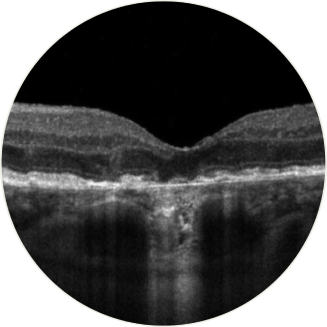

Exame de TCO horizontal sobre a fóvea

Tomografia de coerência óptica (Optical Coherence Tomography, TCO): a atrofia das camadas da retina pode ser claramente observada com essa técnica de imagem não invasiva.17